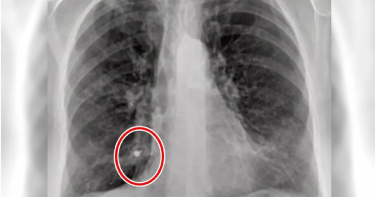

70歲嬤植牙後呼吸不順 檢查驚見「螺絲釘」鑲嵌進肺裡

呼吸不順竟是「螺絲釘」在作怪!西班牙一名70歲婦人,因頻繁的呼吸不順及呼吸道感染問題前往醫院檢查,但結果連醫師也感到驚訝,因為婦人肺部內竟有1根9毫米長的螺絲釘,所幸手術後婦人已無大礙。據《紐約時報》報導,「Vithas Vigo」醫院對飽受呼吸問題困擾1年的婦人進行X光檢查,卻在其中一片肺葉內側近底部位置,發現一塊外型奇特的白點。醫師在後續的支氣管鏡檢查中,驚覺白點真面目是9毫米長的金屬螺絲,且已「鑲嵌」進呼吸組織中。該院醫師除成功取出螺絲釘,也從婦人過去就診紀錄發現,婦人疑似在8個月前「植牙時不小心吸入螺絲釘」,當時的牙醫診所可能在替她裝上2個植入物後安裝癒合帽(healing abutment)過程中,不慎讓螺絲釘被婦人吸進肺部,從而導致她呼吸不順、急促,以及呼吸道感染。幸好,婦人手術後恢復情況良好也已出院,而這起案例並非人類吸入金屬異物的首例,2022年9月就有名患者被告知肺部有個鼻環,當事人這才驚覺「不見5年」的鼻環,竟一直在自己的肺裡。